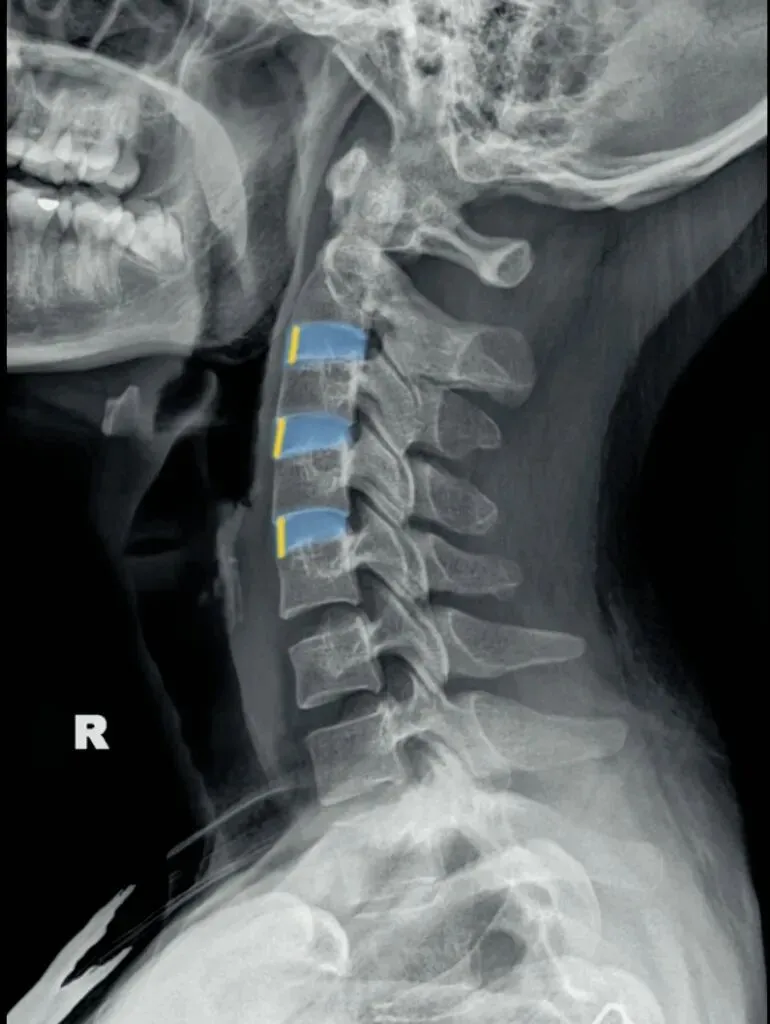

五间是指颈椎椎间隙的变化,主要在颈椎侧位片上观察椎间隙变化同时也反映了椎间盘的变化。

颈椎的退变最早发生在C56椎间盘上,因此C56椎间隙也最早发现变窄的征象。

颈椎骨性椎体为前低后高,

而椎间盘则为前高后低,因此颈椎的生理性前凸是由椎间盘的前高后低所形成的。

在正常情况下,C23、C34和C45间隙大致相等,椎间隙前部为3.8毫米正负0.5毫米,

后缘间隙为1.9毫米正负0.28毫米。

C56间隙较上为宽,而C67间隙最宽,但C7与T1间隙又较窄。